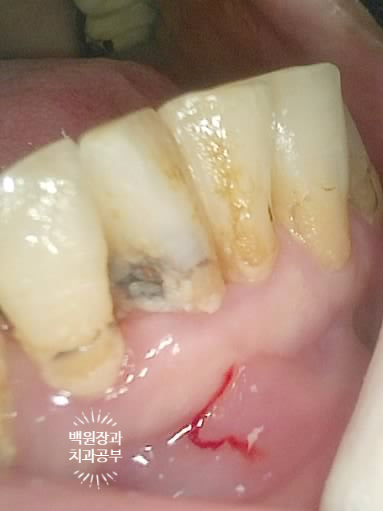

아까 말씀드렸듯, 왼쪽 위 송곳니와 오른쪽 아래 작은어금니에 뿌리만 있는 잔존치근이 관찰됩니다.

개인적으로 이를 뽑으면서 동시에 심어내는 발치 즉시 임플란트에 보수적인 의사입니다만,

이렇게 비록 치아가 썩어서 부러졌을지언정 만성치주염없이 건강한 잇몸뼈를 가지신 분은 충분히 고려해볼만 하죠!!

좌측은 위턱 사진, 오른쪽은 아래턱 구강내 사진입니다.

아주 어렵지 않게 두 치아가 부러져 있다는 것을 확인할 수 있죠.

이뽑으면서 동시에 임플란트를 심으려면 가장 중요한 1조건은, 임플란트가 위치될 부위의 잇몸뼈가 '애당초' 넉넉해야한다는 것입니다. 그래서 너~무 염증이 심했던 치아는 뽑으면서 임플란트 하기가 곤란하고, 설령 해내더라도 예후가 좋지 않아요.

본 70대 여자 환자분의 경우, 치아가 부러지긴 했지만 실질적으로 내부에 염증이 심하지 않았고 송곳니와 작은어금니 모두 비교적 작고 짧은 형태의 뿌리를 갖고 있었기에 발치 동시 임플란트 수술을 계획했습니다.